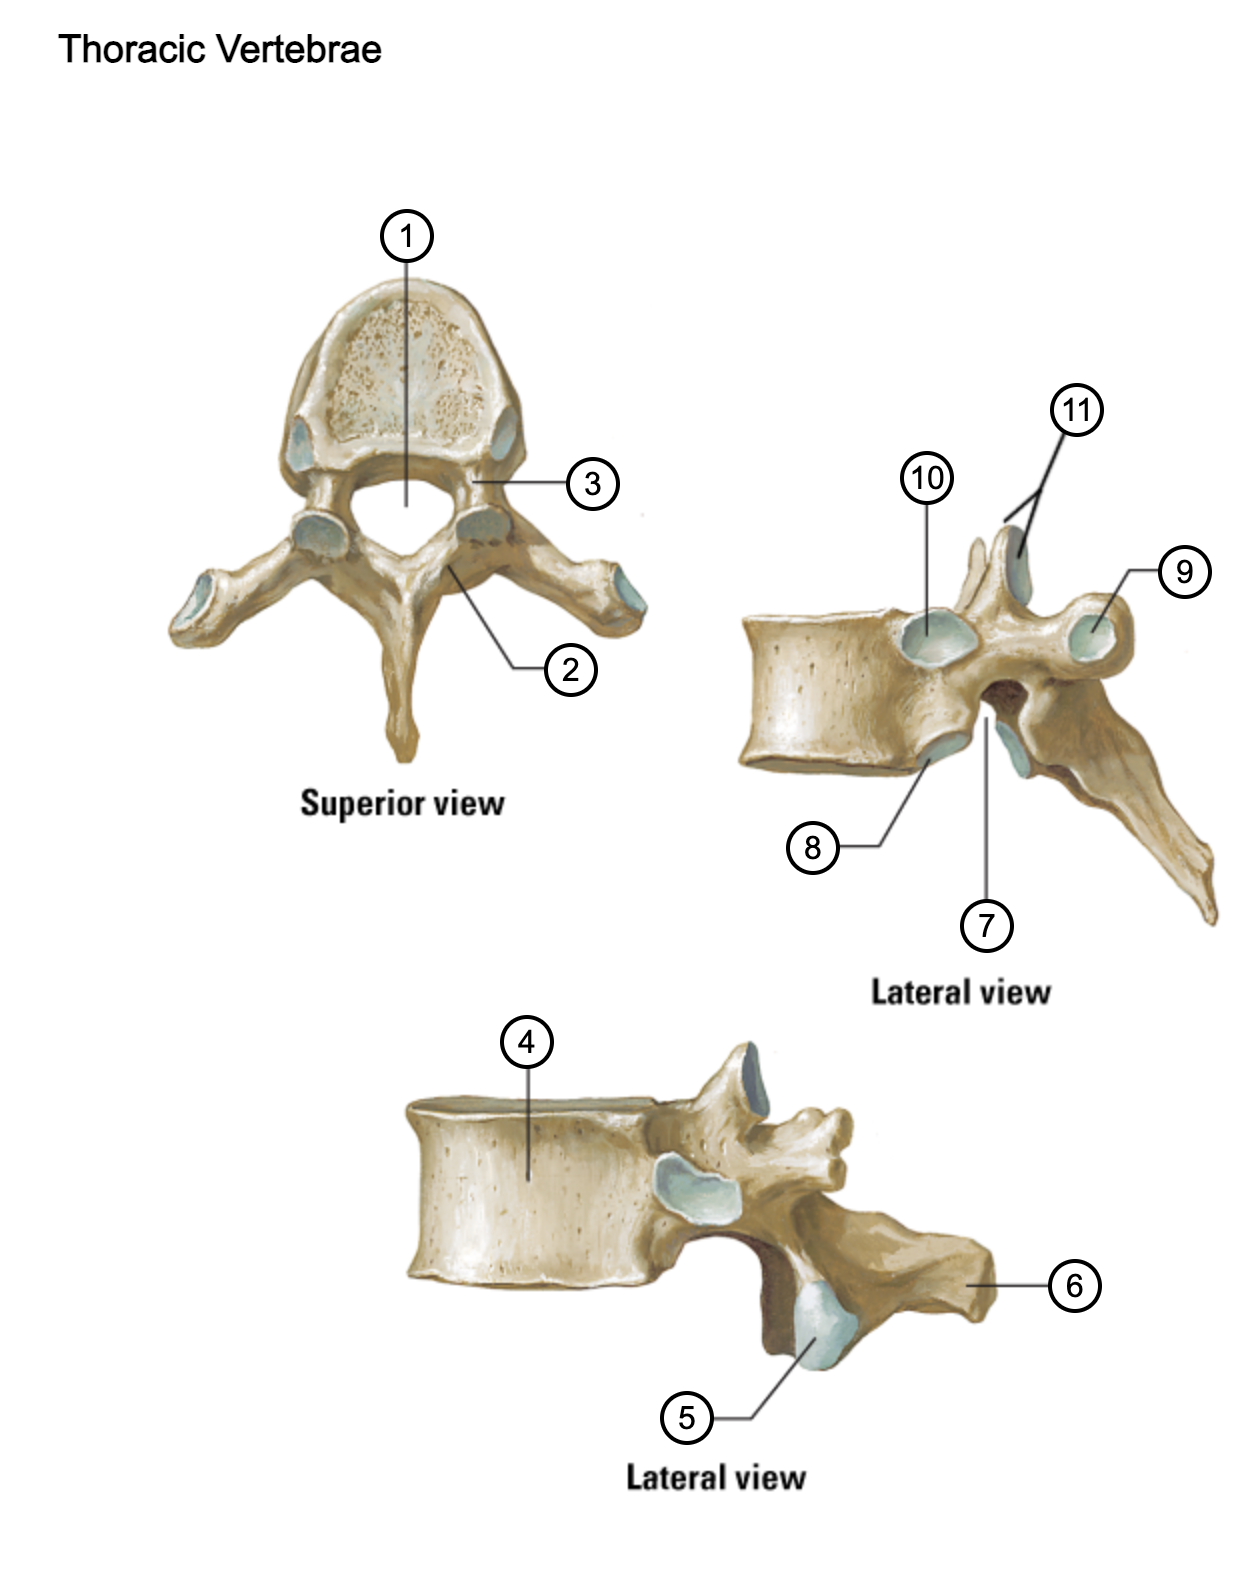

1

vertebral foramen

2

lamina

3

pedicle

4

body

5

inferior articular process and facet

6

spinous process

7

inferior vertebral notch

8

inferior costal facet (for rib articulation)

9

transverse costal facet (for rib articulation)

10

superior costal facet

11

superior articular process and facet